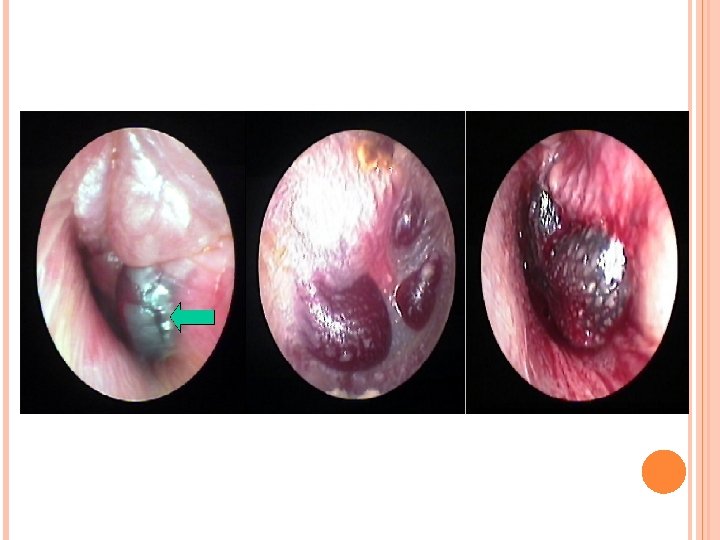

Otitis externa por Herpes simple Afectación cutánea con vesículas del oído externo por virus herpes simple, que no debe confundirse con el herpes zoster. Puede aparecer también en los labios y suele ocurrir cuando hay episodios de fiebre o stress. Es de evolución autolimitada y puede tratarse con aciclovir Miringitis bullosa Infección en la que aparecen vesículas hemorrágicas dolorosas en la cara externa del tímpano. El motivo de incluirla en las otitis externas es porque, aunque el oído externo está compuesto por el pabellón auricular y el CAE, también se incluye la capa externa epidérmica de la membrana timpánica. Suele ocurrir en el transcurso de una infección vírica, como catarro común. Se relaciona con rinovirus, virus influenza. Cursa con otalgia, y se produce una serosidad sanguinolenta cuando se rompen las bullas. Tratamiento con antibióticos, antiinflamatorios y analgésicos.